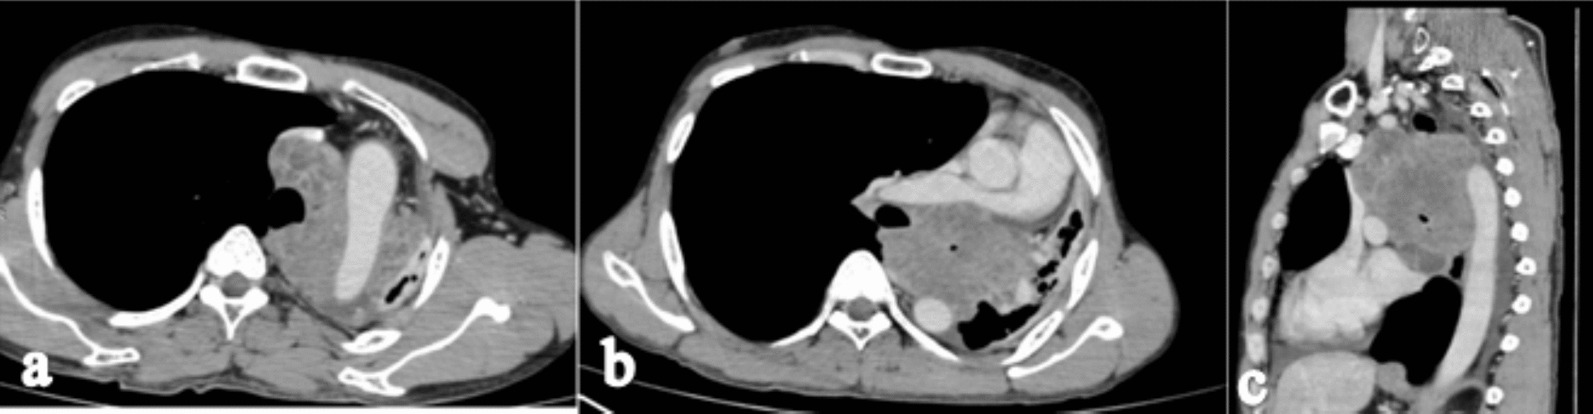

High-resolution computed tomography (HRCT) of the chest in the lung window shows cut off of the left main bronchus with a soft tissue lesion in the upper lobe of the left hemithorax (Fig. 2a). Contrast enhanced CT (CECT) of the chest axial section shows a well-defined lobulated heterogeneously enhancing mass of size 9 × 8 × 7 cm in the left upper lobe with its epicenter in the left main bronchus with complete occlusion of the left main bronchus (Fig. 2b). CECT chest coronal section shows a complete collapse of the left upper lobe with an ipsilateral shift of mediastinum and compensatory hyperinflation of the right lung with minimal left-sided pleural effusion (Fig. 2c). There was no mediastinal lymphadenopathy. CECT axial section shows complete encasement of the aortic arch (Fig. 3a), 150° encasement of the right pulmonary artery with its narrowing (Fig. 3b), and sagittal section shows > 180° encasement of the descending aorta (Fig. 3c).

Fig. 3.

Contrast-enhanced computed tomography axial section shows complete encasement of the arch of aorta (a), 150° encasement of the right pulmonary artery with narrowing (b), and sagittal section shows > 180° encasement of descending aorta (c)